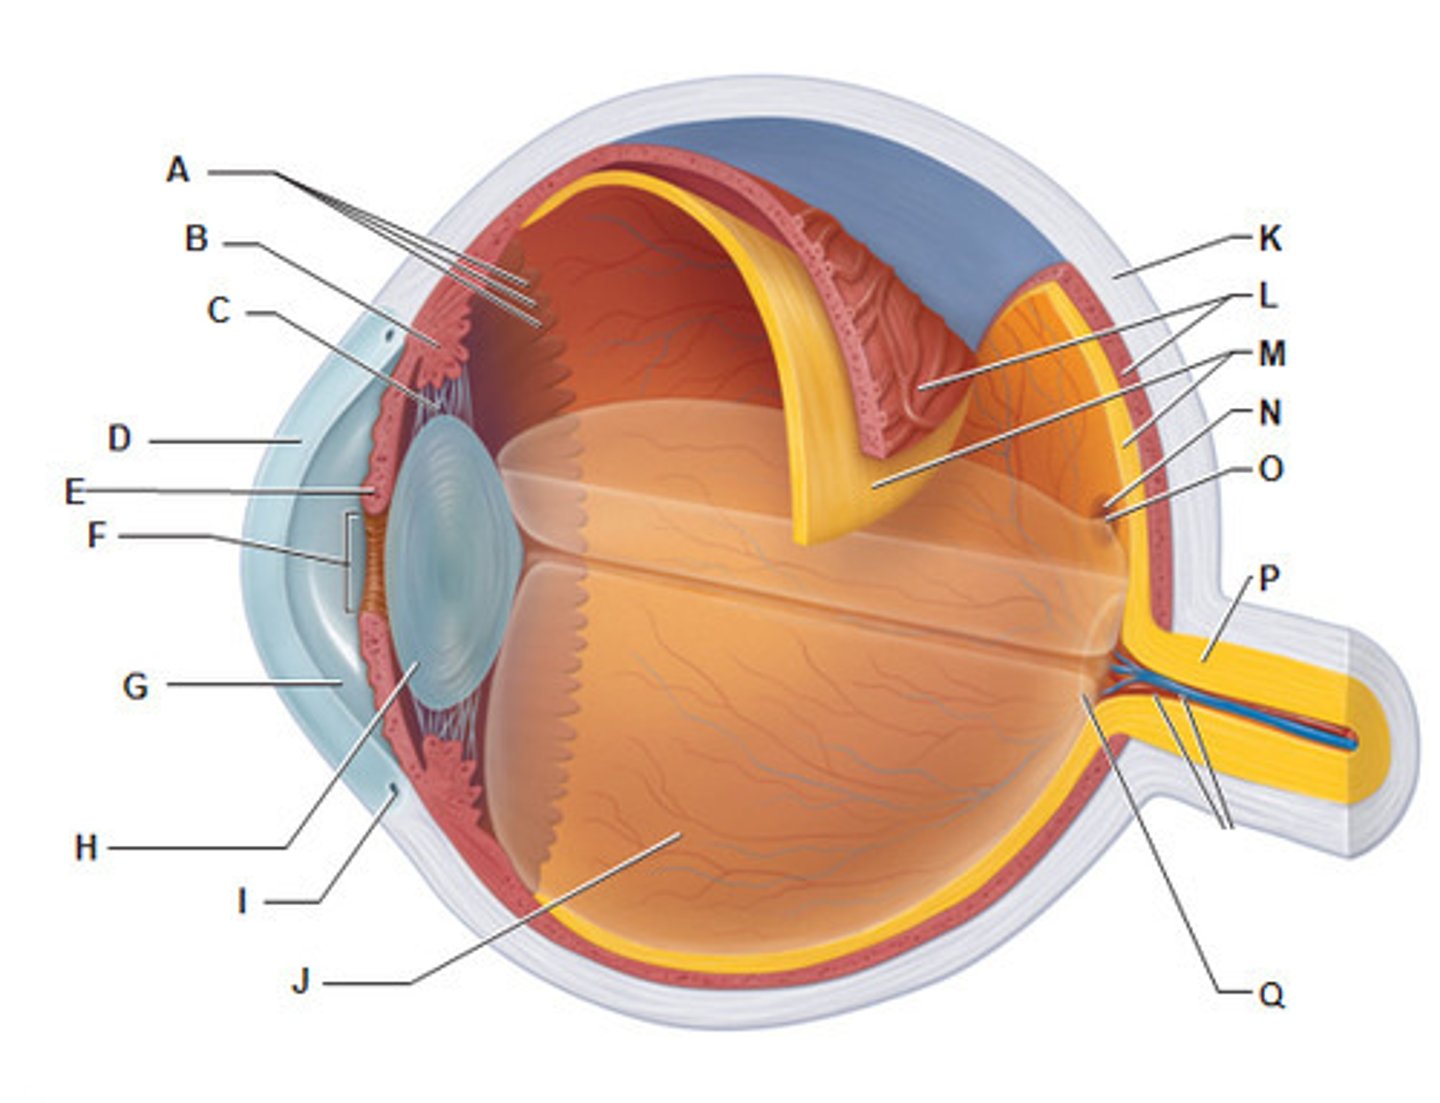

anterior cavity (of eye)

iris

optic disk (blind spot)

choroid

L

ciliary body

conjunctiva

cornea

D

fovea centralis

suspensory ligaments

vitreous humor

lens

H

macula lutea

posterior cavity (of eye)

pupil

retina

M

sclera

optic nerve